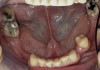

Figure 1  Intraoral anterior view of the patient presenting a severely worn maxillary dentition and loss of OVD.

Figure 1

Initial examination revealed a partial edentulous patient with extensive wear of the maxillary anterior teeth and moderate wear in the mandibular teeth (Figure 1, Figure 2, Figure 3 , Figure 4, Figure 5, Figure 6 and Figure 7). The patient's maxillary and mandibular RPDs also showed excessive wear and multiple signs of fractures (Figure 2 and Figure 3). The patient had been wearing a mandibular nightguard for 8 years.

A history of bruxing and consumption of acidic and carbonated drinks were reported. The clinical examination revealed severe tooth wear extending to the cervical level of the palatal surfaces of the maxillary teeth in some areas. Therefore, TSL was diagnosed as being caused by a combination of attrition and erosion.